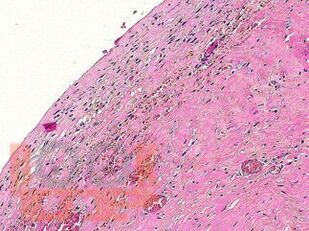

В атласе подробно изложено цитологическое и гистологическое описание всего спектра патологических изменений ткани молочной железы: неопухолевые, пролиферативные процессы, предраковые поражения, доброкачественные и злокачественные опухоли. Кратко представлены данные об этиологии, о патогенезе, молекулярной генетике, клинической картине и лучевых методах исследования различных поражений молочной железы. Подробно описаны дифференциальная диагностика и возможные ошибки морфологической диагностики. Атлас иллюстрирован большим количеством микрофотографий.

Традиционная морфология имеет фундаментальное значение в диагностической патологии. Атлас представляет собой реферативный текст, в котором обобщены имеющиеся на данный момент основные знания о патологии молочной железы, собранные из различных источников, и собственный опыт авторов. Текст построен в виде коротких фраз, постулирующих ключевые моменты различных поражений молочной железы.